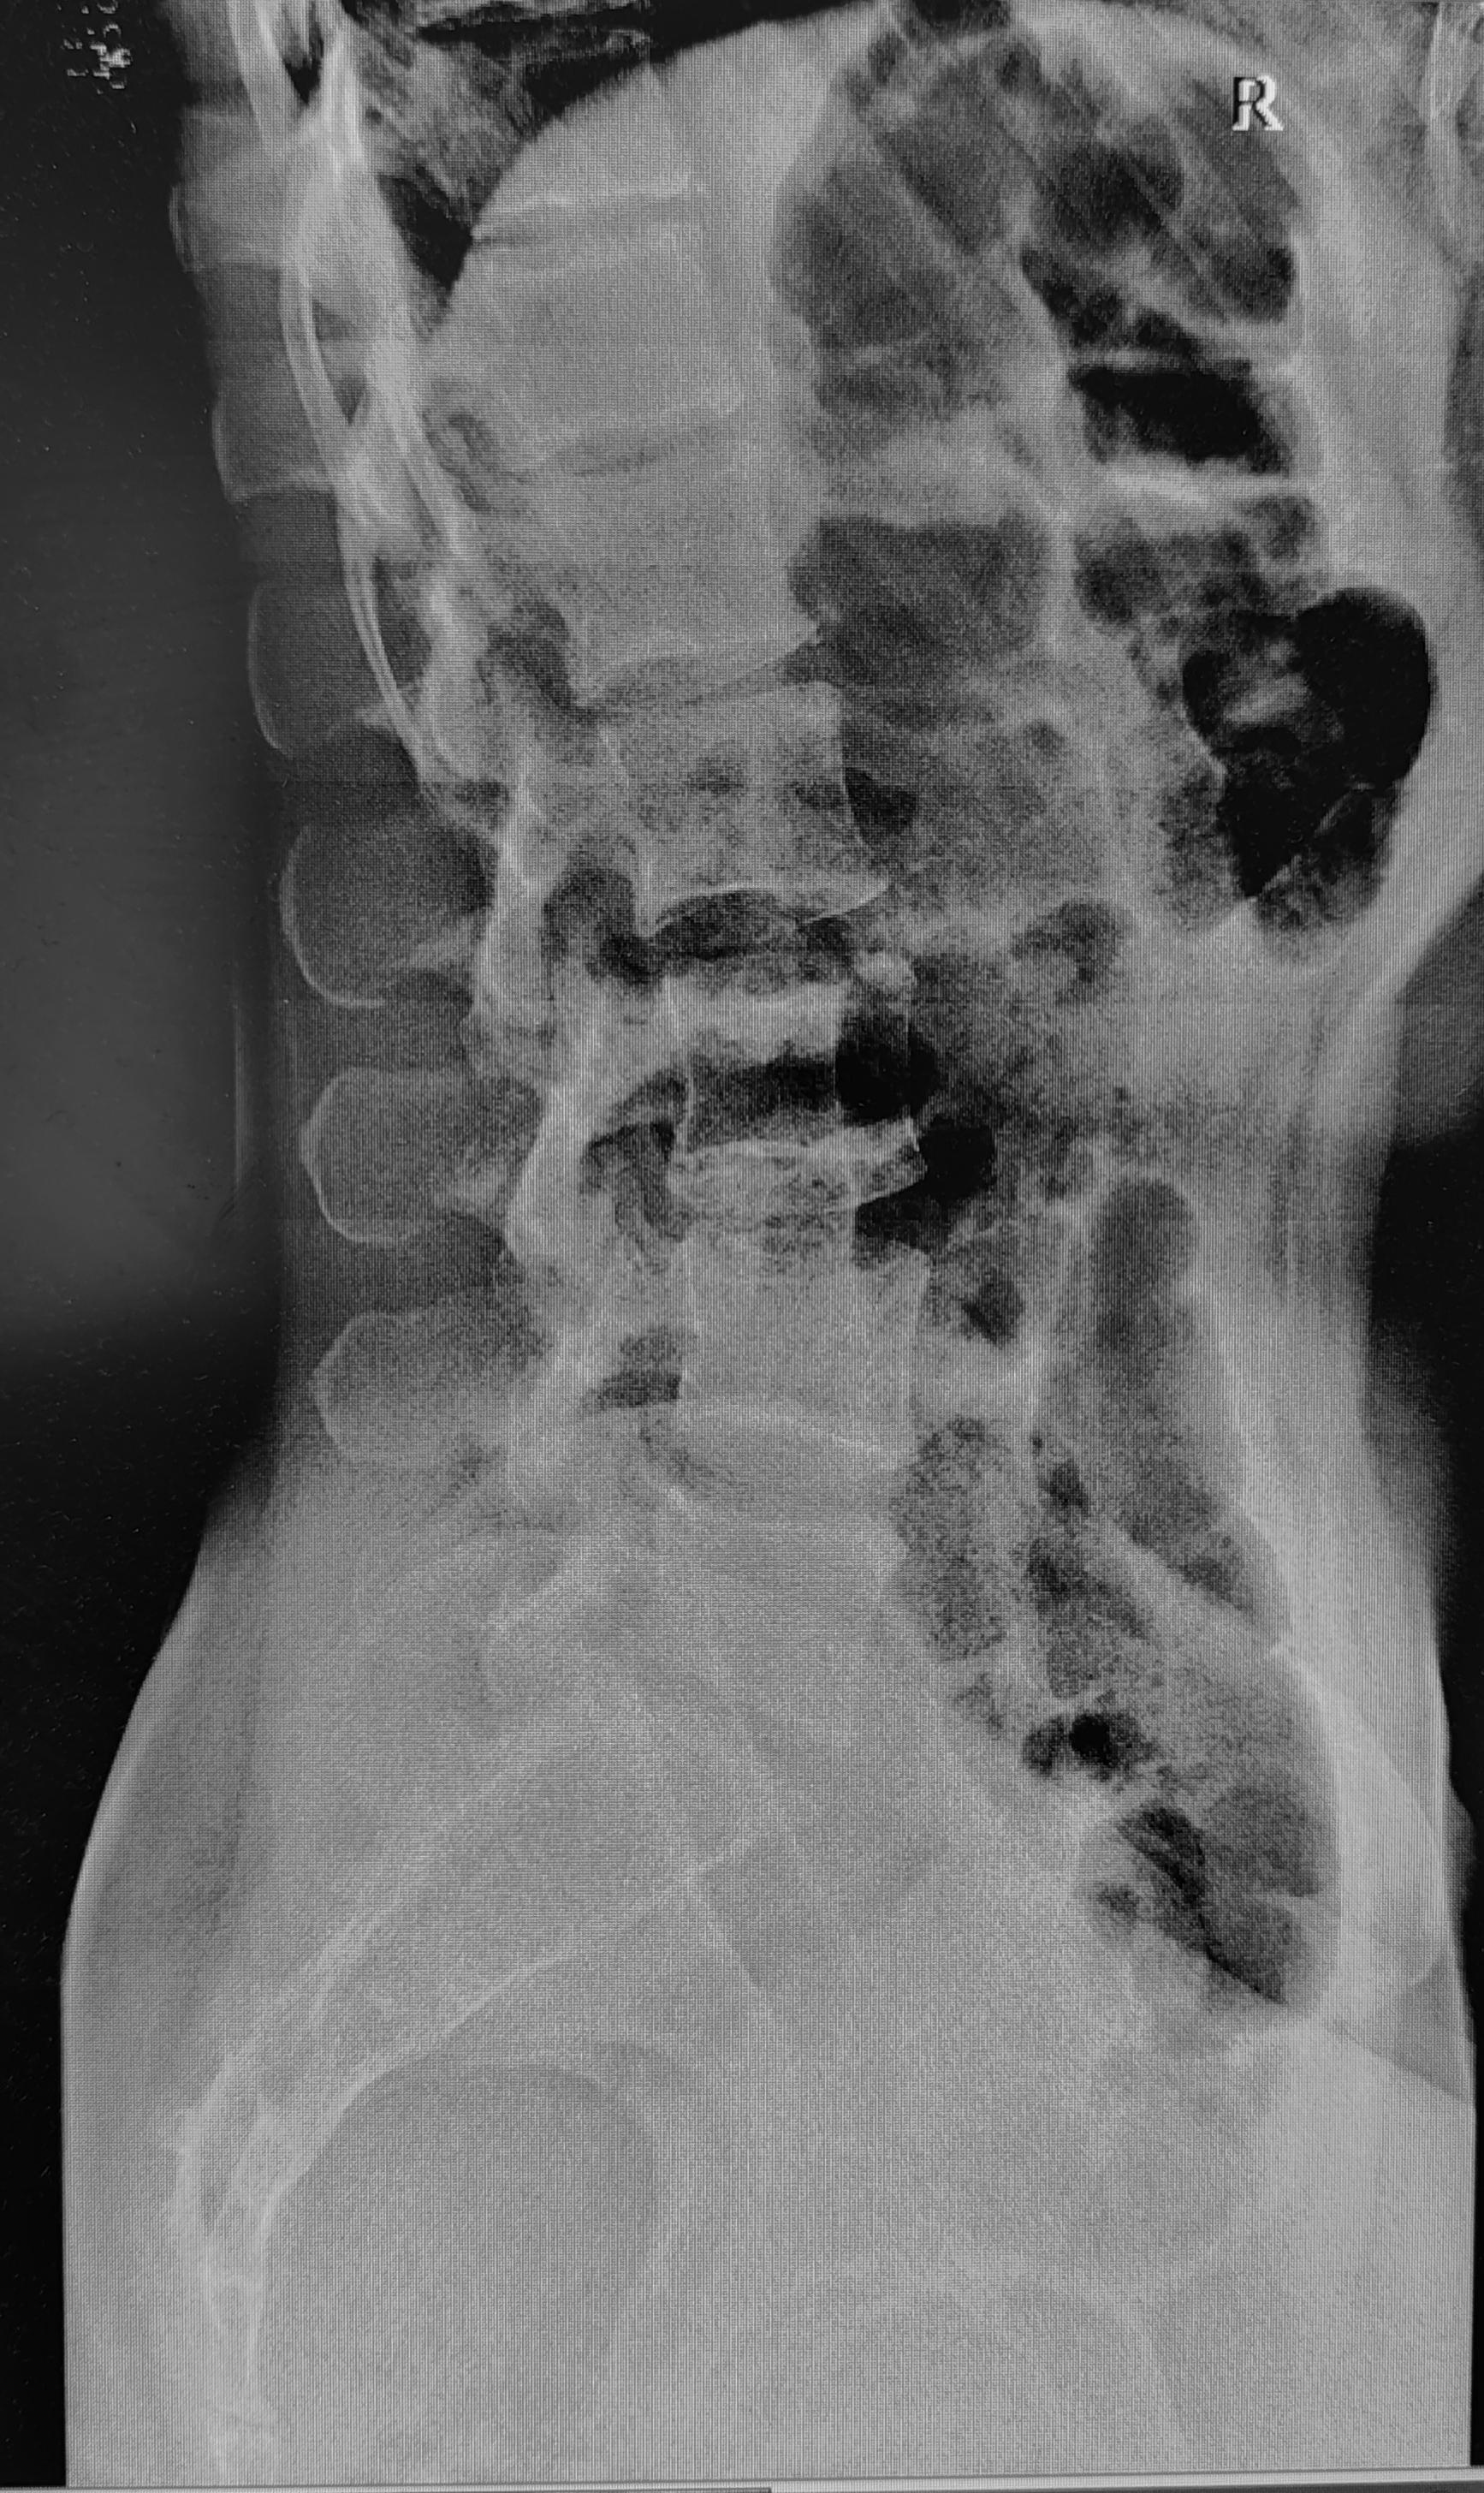

Рентгенограммы поясничного отдела позвоночника пациента с длительным, выраженным болевым синдромом(6 мес.) в пояснице, с временным эффектом от приема НПВС. При описании снимков выраженной костной патологии в поясничном отделе позвоночника не выявлено: структура тел позвонков не изменена, травматических, деструктивных изменений не выявлено, субхондральный склероз замыкательных пластин тел позвонков отсутствует, краевые остеофиты тел позвонков не выявлены, имеется не выраженное неравномерное сужение межпозвонковых щелей как начальное проявления остеохондроза-такая рентгенологическая картина не дает столь выраженного и длительного болевого синдрома.

Обращают на себя внимание крестцово-подвздошные сочленения(КПС),отмечается неравномерное не выраженное сужение щелей КПС с локальными участками расширения, субхондральный склероз- более выраженный слева, имеются двусторонние краевые остеофиты, в нижней трети левого КПС суставная щель не ровная, "изъеденная", по причине наличия единичных эрозий костной ткани. Заключение: Двусторонний сакроилиит 2 ст.(более выраженный слева).